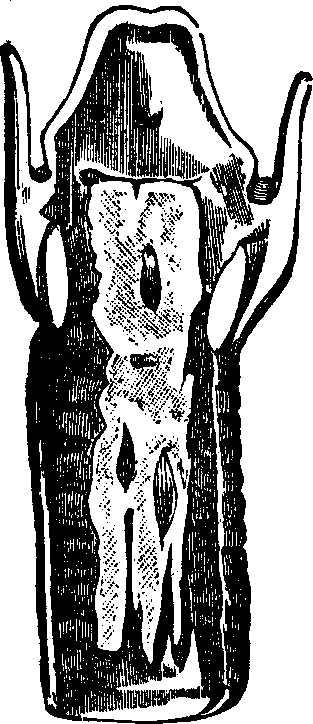

Fig. 3. THE UTERINE DILATOR. This instrument is introduced

into the canal of the uterine neck with its blades closed. By means of the

thumb-screw the blades are then separated as shown in this illustration,

the cervical canal being thereby dilated to the required extent.

Treatment. From the nature of this malady, it will readily be seen that no medical treatment can effect a radical cure. We must therefore resort to surgery. In a small proportion of cases, the stricture may be cured by repeated dilations of the constricted part of the cervical canal. This may be accomplished by using a very smooth probe which is fine at the point, but increases in size, so that its introduction will widen and expand the orifice and canal. The stricture may be overcome in many cases by using different sized probes. In some instances, we have employed the uterine dilator, represented by Fig. 3. We have also introduced sea-tangle and sponge tents into the neck of the womb, and allowed them to remain until they expanded by absorbing moisture from the surrounding tissues. The latter process is simple, and in many cases preferable. By means of a speculum (see Figs. 15 and 16), the mouth of the womb is brought into view, and the surgeon seizes a small tent with a pair of forceps and gently presses it into the neck of the womb, where it is left to expand and thus dilate the passage. If there seems to be a persistent disposition of the circular fibers of the cervix to contract, and thus close the canal, a surgical operation will be necessary to insure permanent relief. In performing this operation, we use a cutting instrument called the hysterotome (see Figs. 4 and 5). By the use of this instrument, the cervical canal is enlarged by an incision on either side. The operation is but slightly painful, and, in the hands of a competent surgeon, is perfectly safe. We have operated in a very large number of cases and have never known any alarming or dangerous symptoms to result. After the incision, a small roll of cotton, thoroughly saturated with glycerine, is applied to the incised parts, and a larger roll is introduced into the vagina. The second day after the operation, the cotton is removed, the edges of the wound separated by a uterine sound or probe, and a cotton tent introduced into the cervix, and allowed to remain, so that it will expand and thus open the wound to its full extent. This treatment must be thoroughly applied, and repeated every alternate day, until the incised parts are perfectly healed.